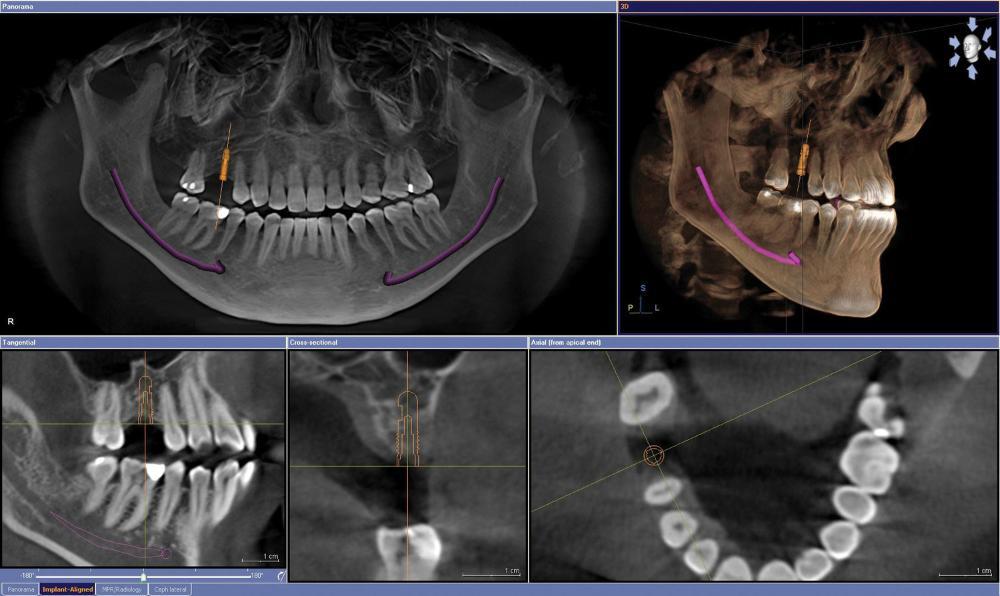

- Your dental team will take a series of photos, impressions, bite records and radiographic scans to get a full understanding of your dental anatomy so that a custom plan can be devised

On the day of your implant procedure, the dentist can remove any diseased teeth and complete any bone augmentation required. The dentist will place the implants (usually between 4 and 6 implants). Once the anchoring of the implants has been verified, the custom full-arch restoration can be placed into the mouth and secured to the implants.